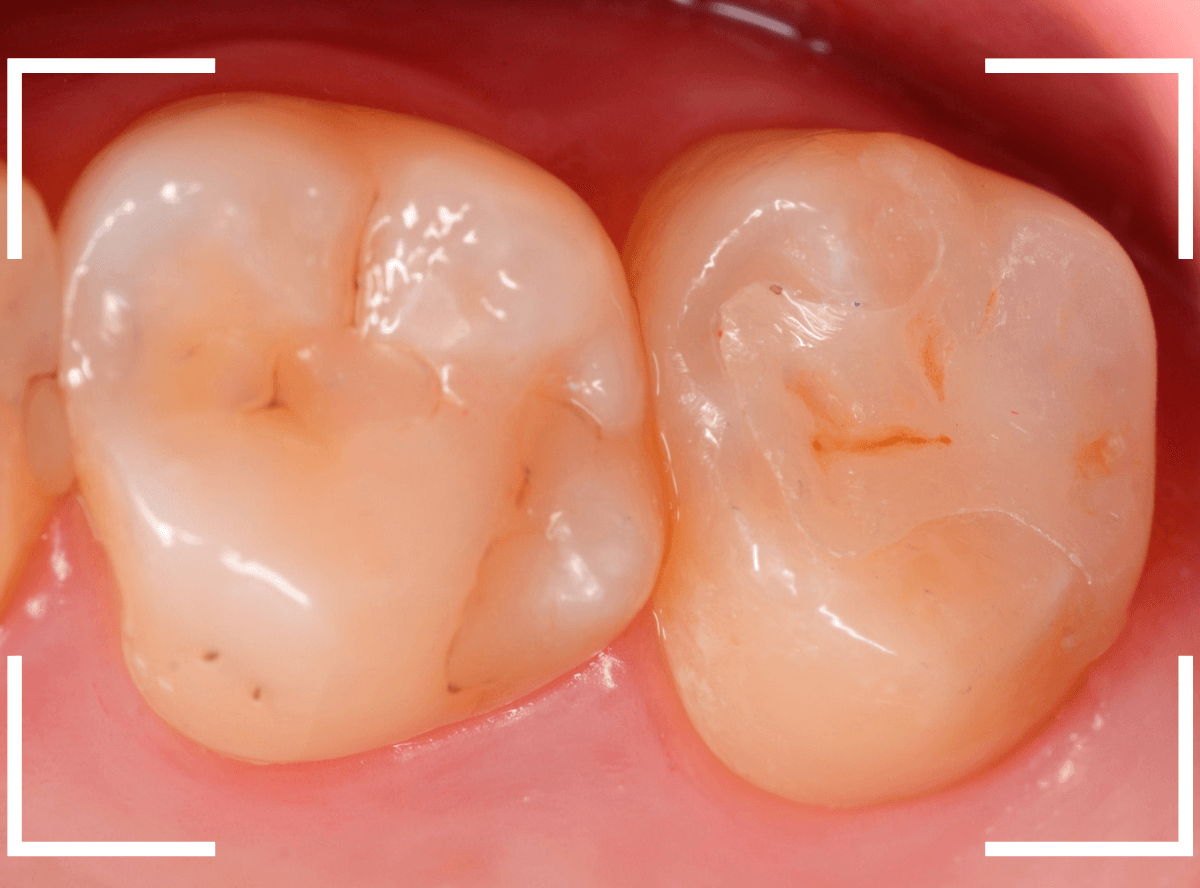

Case.3 上の一番奥の部分が深い虫歯!2

こちらも、上の奥歯の奥側が大きな虫歯になってしまった方です。

他の歯の治療を希望されて来院されたのですが、こちらの虫歯については本人には全く自覚がありませんでした。

しばらく経過観察した後、特に症状もなく経過しましたので、型を取ってつめもの(インレー)で歯の形を仕上げます。

今回は、できるだけ良い素材での治療をご希望されましたので、ジルコニア・インレーでの治療となりました。

型を取った製作した模型上でジルコニア・インレーを製作します。

お口の中でsetしたところです。

ほとんど調整する事もなく、ピッタリと合わせる事ができました。